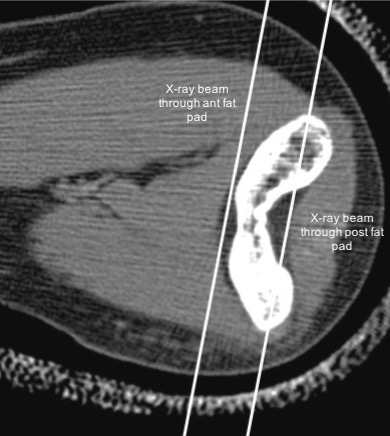

- Posterior fat pad of the elbow lies deep within the olecranon fossa while the anterior fat pad is not flanked by bone on either side (see figure below). Hence, on a lateral radiograph, the anterior fat pad should be normally visible and the posterior fat pad should not be visible (see figure below).

- If there is an elbow effusion, it pushes both the fat pads outside, so that the posterior fat pad is no longer masked by the supracondylar ridges and becomes visible on the radiograph. The anterior fat pad which was normally seen adjacent to the humerus, gets lifted up inferiorly and a fluid fat interface can be seen (sail sign).

- Do note that if the elbow effusion is very large, both the anterior and the posterior fat pads may get completely effaced and not visible (false negative). However, you should be able to see significant soft tissue swelling in such cases and make the diagnosis (figure below).